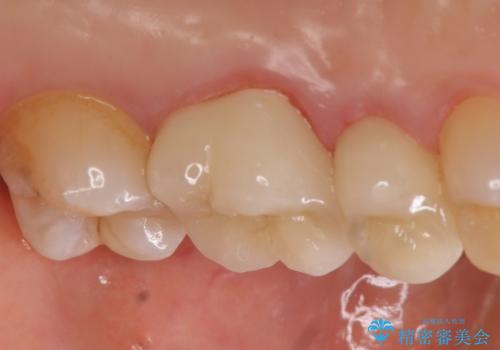

痛みの消失を確認後、オールセラミッククラウンによる補綴を行いました。

今回用いたオールセラミッククラウンはジルコニアフレームという白い素材の上にセラミックを盛っているため、審美性が非常に高いのが特徴です。

また、ジルコニアは人工ダイヤモンドの材料にも使われているほど高い強度を持っており、そのためオールセラミッククラウンは審美性だけでなく、奥歯やブリッジの補綴も可能とするクラウンです。